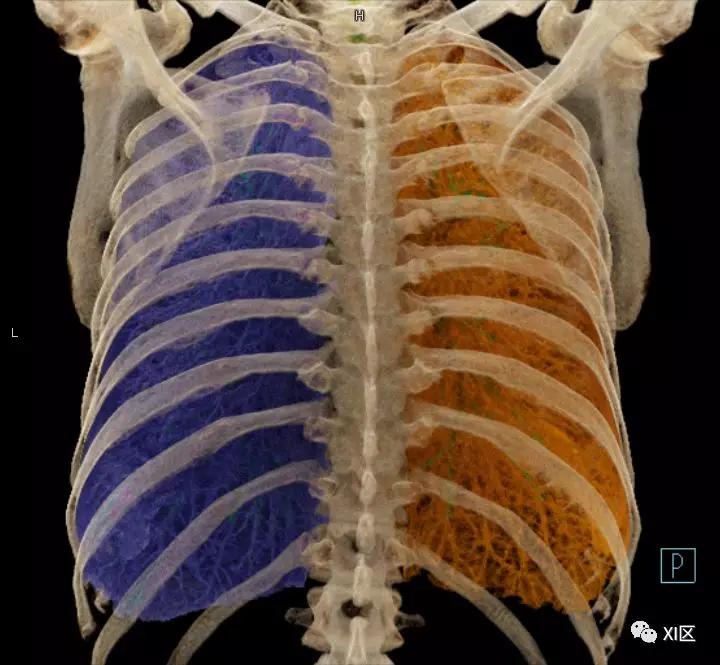

前后位,双侧位,后前位显示气道肺与胸部骨骼的关系

肺的分叶

左肺借斜裂成上、下两叶;右肺借斜裂和水平裂成上、中和下叶三叶。

肺表面重建显示叶间裂和肺的分叶

透视图显示肺的叶间裂和肺的分叶